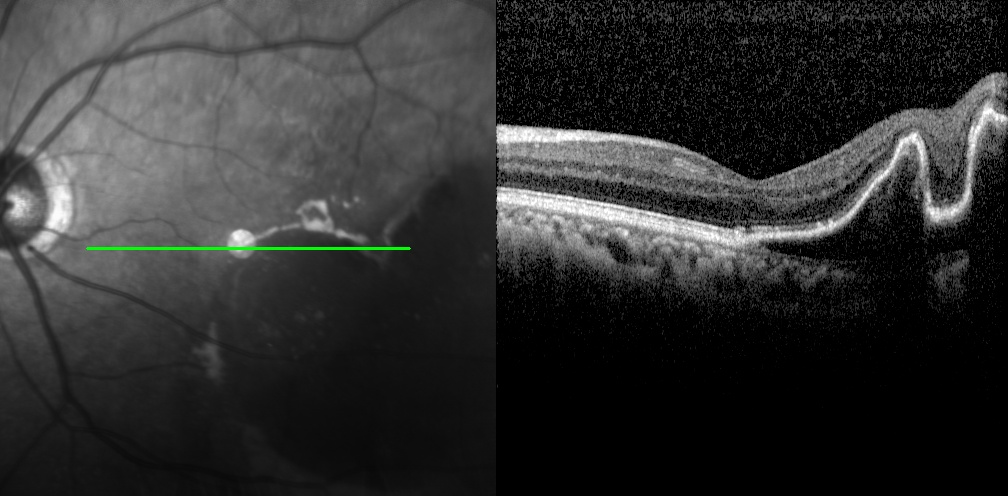

老王左眼檢查圖片

黃斑變性

左眼調(diào)整用藥半個(gè)月后檢查圖片